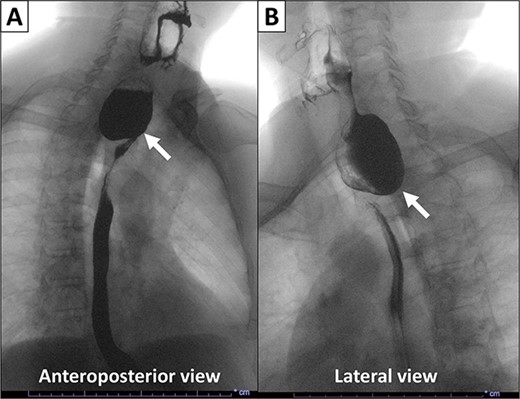

Pre-operative computed tomography imaging demonstrated a 5.0 × 4.4 × 2.4 cm diverticulum off of the proximal posterior esophagus, consistent with a ZD. In addition, a barium swallow revealed a large posterior esophageal diverticulum with significant residual contrast within the diverticulum lumen. Given these findings, the patient was taken for open surgical excision or Zenker diverticulectomy. A large exophytic and ulcerated mass was identified within the diverticulum (Fig. 2). The specimen was sent to pathology. A frozen section of the mass was obtained revealing SCC.

Gross images of the diverticulectomy specimen. (A) Exophytic and ulcerated mass identified within the Zenker’s diverticulum. (B) Sectioning across the mass showed a white cut surface involving the full thickness of the esophageal wall and grossly abutting the serosal surface.